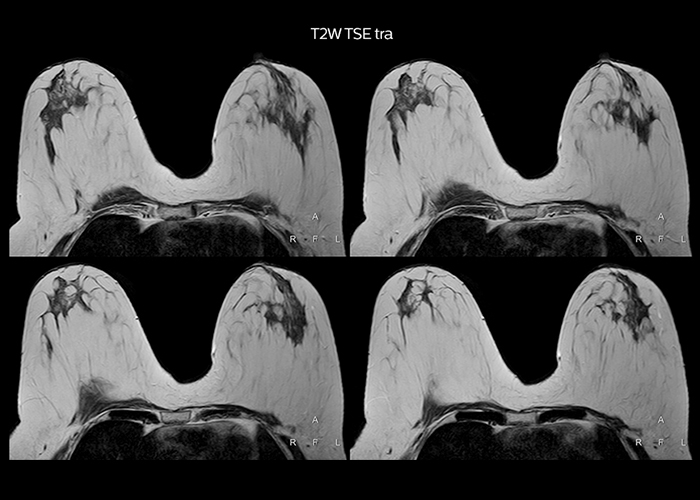

“On average, we scan about 80 patients per day, but on some days we scan well over 100 patients. The scanner is in use 7 days per week, operated 20 hours per day on week days and 8 hours per day in the weekend,” Mr. Tuna says. “To avoid coil changes we plan examinations of similar anatomies back to back, such as head and spine. Multiva helps us here a lot because coils don’t need to be changed frequently. Moreover, thanks to parallel imaging technology and 16-channel HeadSpineTorso and 8-channel MSK coils we are able to achieve excellent image quality. In this way Multiva helped us to increase both image quality and productivity.” “Neurological cases, such as brain and spine imaging, represent the largest share in our MR scanning, followed by musculoskeletal cases. In general, we use simple and basic imaging protocols. But occasionally, we use advanced techniques for problematic cases if necessary.

“Since we have Multiva, we have improved our workflow, because it has been so easy for our operators to learn and use Multiva. Our operators notice that the coils are lightweight and coils don’t need to be changed frequently. The user interface is easy to use. Features like this help us to scan a high number of patients. For instance, the musculoskeletal coils can be used interchangeably, and due to the user-friendly interface, the number of mistakes such as, for example, correct coil element selection has decreased significantly, because the system does it automatically by itself.” “Most important, Multiva satisfies our clinical imaging needs very well,” says Mr. Tuna. “Many features of Multiva have become similar to the Ingenia system. Even in more complex imaging such as abdominal and cardiac, the image quality and performance of Multiva is better than we expected. General surgeons and physicians from our hospital’s internal medicine department prefer to refer to us because of this.”